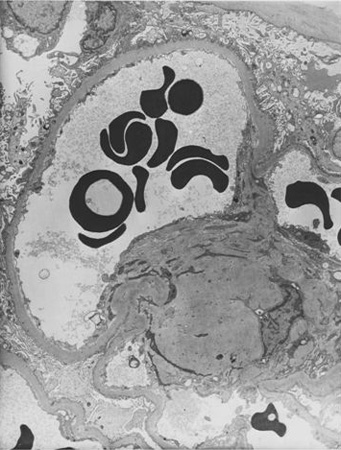

Diabetic kidney disease

Diabetic kidney disease: at 5 o'clock - early Kimmelstiel-Wilson nodule, a rounded increase in mesangial matrix that probably originated in relation to a microaneurysm

From the collection of Dr Raoul Fresco; used with permission